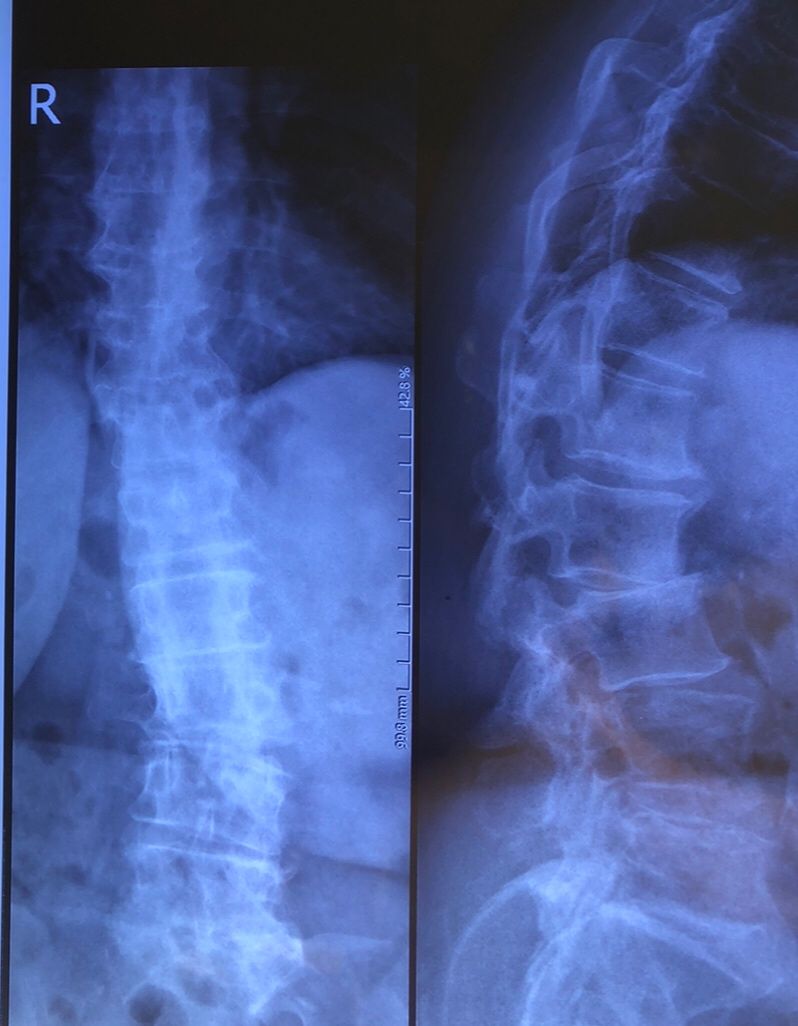

This time presented to my cl with LBP mainly during sleep at night. Just brought me her mri. According to her mri I ordered dynamic L/S X. R.

I didn’t accept her to give treatment. I referred her to her surgeon. What are your findings in her mri and X. Rays?

Is ant listhesis of L4 unstable or stable?

From several compression fractures we see which of is acute/ subacute and which ones are chronic fx?